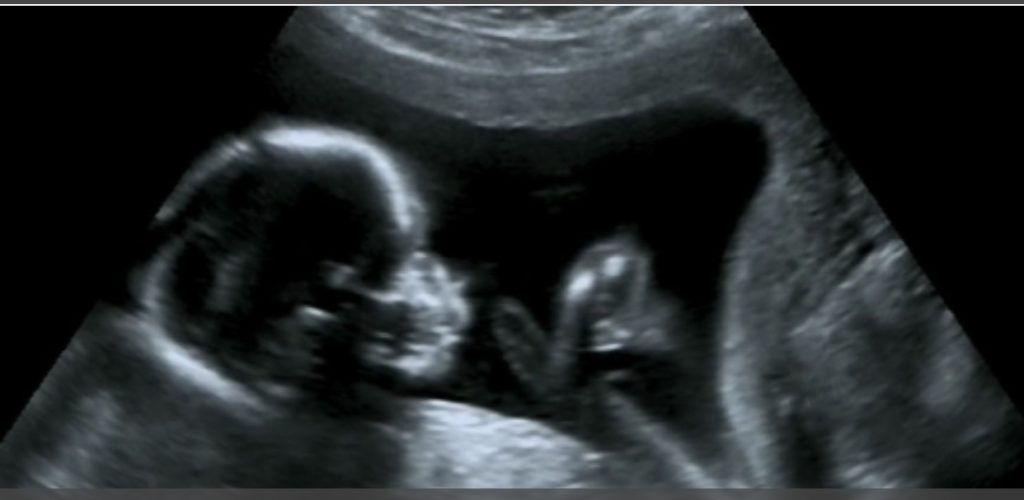

كشف باحثون من جامعة فيرارا الإيطالية، في دراسة نشرت بمجلة PLOS One، أن الأجنة الذين يكثرون من التثاؤب بين الأسبوعين 23 و31 من الحمل قد يكونون أكثر عرضة لولادة بأوزان أقل نسبيا. واعتمدت الدراسة على مراقبة 32 جنينا بصحة جيدة عبر التصوير بالموجات فوق الصوتية لمدة 22.5 دقيقة لكل جنين، وسجلت معدلات تثاؤب تراوحت بين صفر وست مرات خلال فترة الرصد، بمتوسط 3.6 مرات في الساعة.

ويعرف التثاؤب بأنه سلوك شائع لدى الفقاريات، إلا أن وظيفته الدقيقة عند الإنسان ما زالت غامضة. ويبدأ الجنين بالتثاؤب منذ الأسبوع الحادي عشر من الحمل، حيث يقوم بفتح فمه وحركات تشبه الشهيق والزفير، رغم عدم وجود هواء يتنفسه.